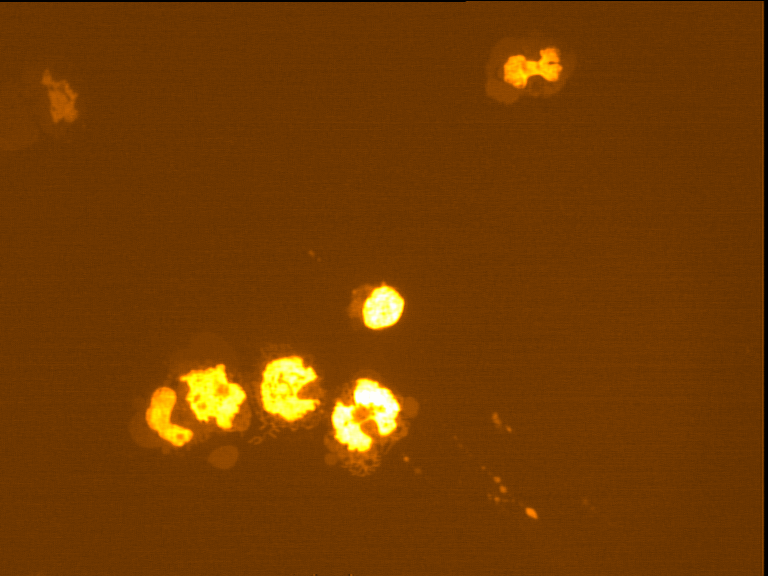

Fig. 4 through 6 show the morphological features of Raji cell sub-lines exposed to DOX, indomethacin, or verapamil. Some of the reversal agents significantly increased the frequency of apoptotic cells compared with control cells. Thus, the P-gp reversal agents were able to overcome apoptotic resistance in the NHL cell-line model. Apoptotic cells in the controls contributed approximately 10% of the whole population (i. e., 61/600 x 100 = 10.16% for TK+ and 69/600 x 100 = 11.5% for TK-). After exposure to the P-gp reversal agents, apoptic cells increased to 22.3% with indomethacin and to 43% with doxorubicin in TK+ cells. In TK- cells, apoptic cells increased from 11.5% to 26.8% and 75.7% with indomethacin and doxorubicin, respectively.

Fig. 6: Morphological features of Raji TK- cells after treatment with indomethacin (1), verapamil (2), and DOX (3). In each row, left images show intact cells, middle images show apoptotic cells, and right images show necrotic cells as they appeared under the microscope X 200